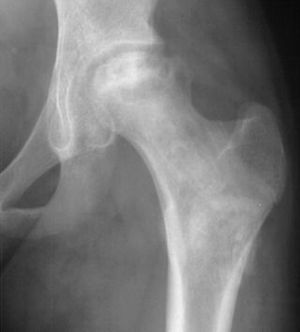

Avasculsr necrosis of the bone is Infarction of bone due to a disruption in blood supply. AVN of bone results from corticosteroid, alcohol, ideopathic, sickle cell anemia, and Gaucher's disease. Most commonly involved bones are femoral head (associated with subcapsular fracture that compromises medial circumflex femoral artery), Humeral head, scaphoid (most commonly fractured carpal bone), digits and talus. Evaluation is by MRI, X-Ray, and bone scan. Treatment is by using bisphosphonates.